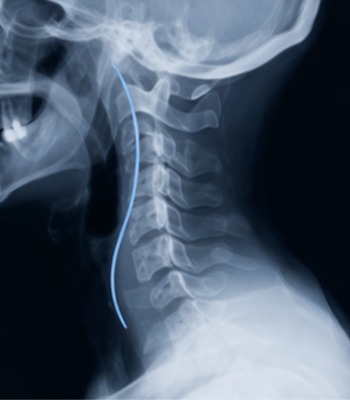

Curvatura Normal

El cuello tiene una elegante curvatura hacia adelante. Los bordes de cada hueso están bien definidos, con el mismo espacio discal entre cada hueso y aperturas nerviosas claras y sin obstrucciones.